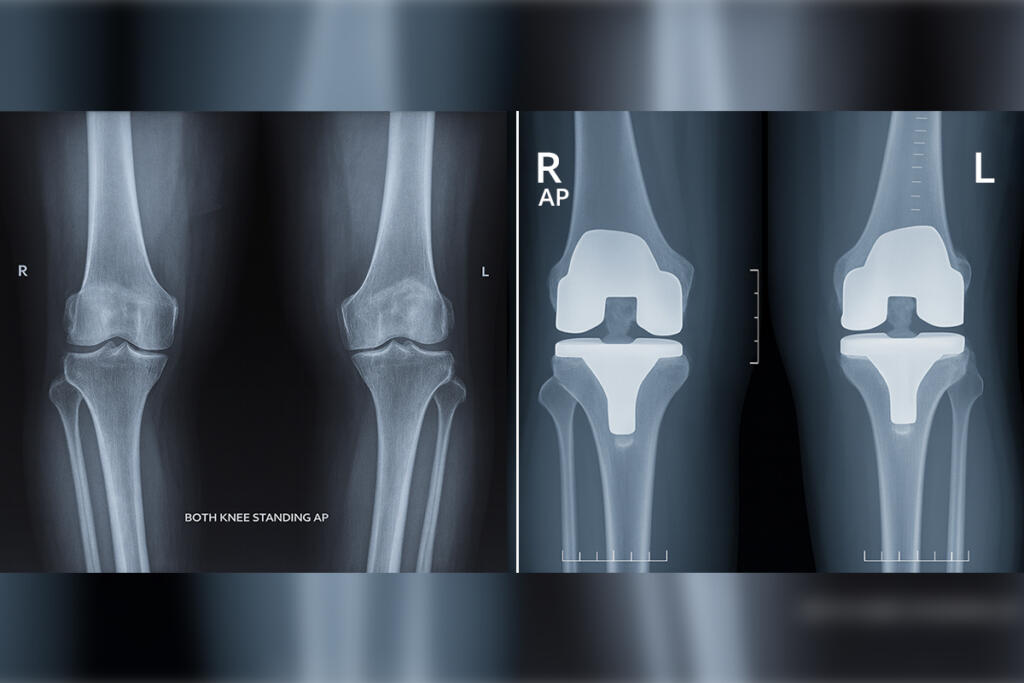

Primary Knee Replacement

Arthritis Treatment

Arthritis is a condition characterised by inflammation and pain in multiple joints, often affecting both sides of the body...